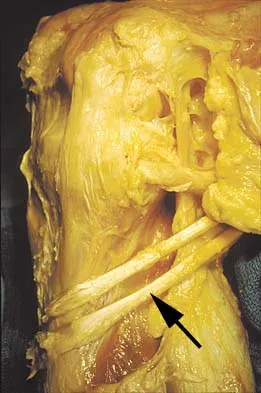

Question 52:

A 21-year-old man has had right groin pain for the past year. A radiograph, CT scan, MRI scans, and a biopsy specimen are shown in Figures 50a through 50e. What is the most likely diagnosis?

Options:

- Chondrosarcoma

- Osteoblastoma

- Chondroblastoma

- Giant cell tumor of bone

- Subchondral cyst

Correct Answer: Chondrosarcoma

Explanation:

The pathology demonstrates a very cellular chondroid matrix with multinucleated forms, atypia, and myxomatous regions. This is most consistent with a myxoid chondrosarcoma. The radiograph shows a well-circumscribed lesion in the superior and medial aspect of the right acetabulum. The CT and MRI scans confirm these same findings with no evidence of matrix mineralization or significant surrounding edema. Unfortunately, in this location with this appearance, the radiographic differential diagnosis includes all the diagnoses listed. Terek RM: Recent advances in the basic science of chondrosarcoma. Orthop Clin North Am 2006;37:9-14. Donati D, El Ghoneimy A, Bertoni F, et al: Surgical treatment and outcome of conventional pelvic chondrosarcoma. J Bone Joint Surg Br 2005;87:1527-1530.